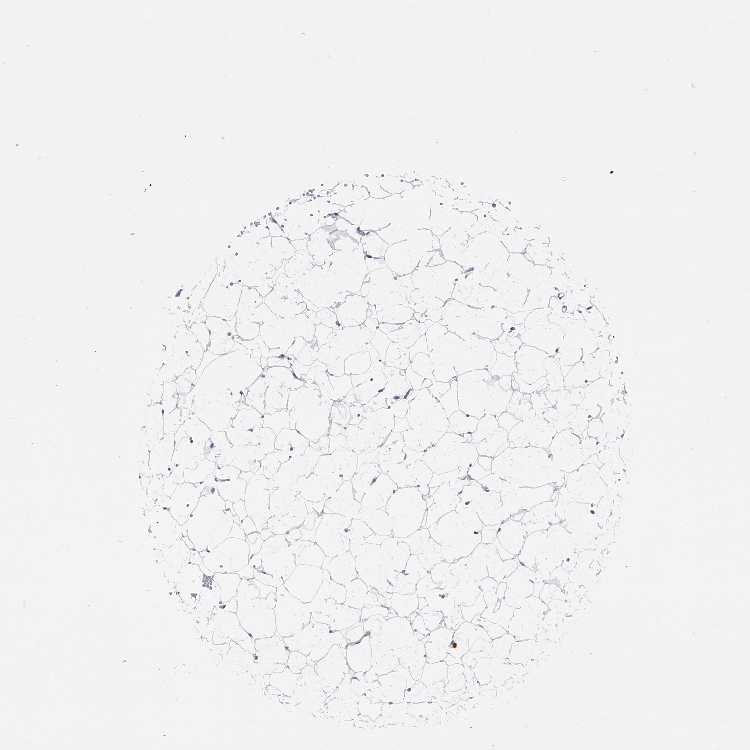

ADIPOSE TISSUE - Antibody stainingi

Antibody staining in the annotated cell types in the current human tissue is reported as not detected, low, medium, or high, based on conventional immunohistochemistry profiling in selected tissues. This score is based on the combination of the staining intensity and fraction of stained cells.

Each image is clickable and will lead to virtual microscopy that enables deeper exploration of all samples and also displays staining intensity scores, fraction scores and subcellular localization as well as patient and tissue information for each sample.

Antibody CAB034107

Adipocytes Not detected